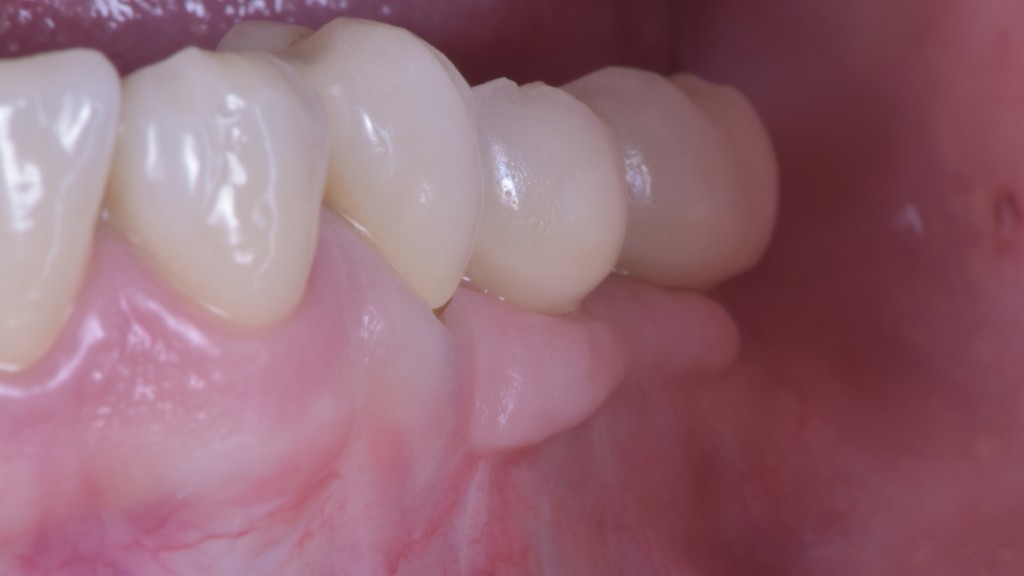

O puoi riabilitare la paziente adeguatamente:

DSC_5588

Ma per fare questo non ci sono polverine magiche di osso di dinosauro o impianti di un millimetro. Ci sono anni di studio, sudore e  sangue (E SGUARONE!!) per noi… e un VAS 2 per la paziente!!!!!!! ?